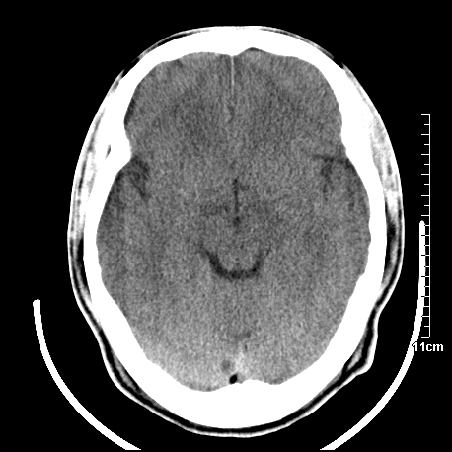

头晕.头痛间断意识恍惚1周 m/21y

右侧放射冠可见点状低密度,可疑腔隙性梗塞

我当时诊断的是1.右侧底节区脑血栓形成

2.考虑少量蛛网膜下腔出血

3.右侧颞叶低密度区考虑脑血管畸形

因病人拒绝进一步检查,反复做工作后,病人做了腰穿,脑脊液化验显示有红细胞,呈现轻度红色